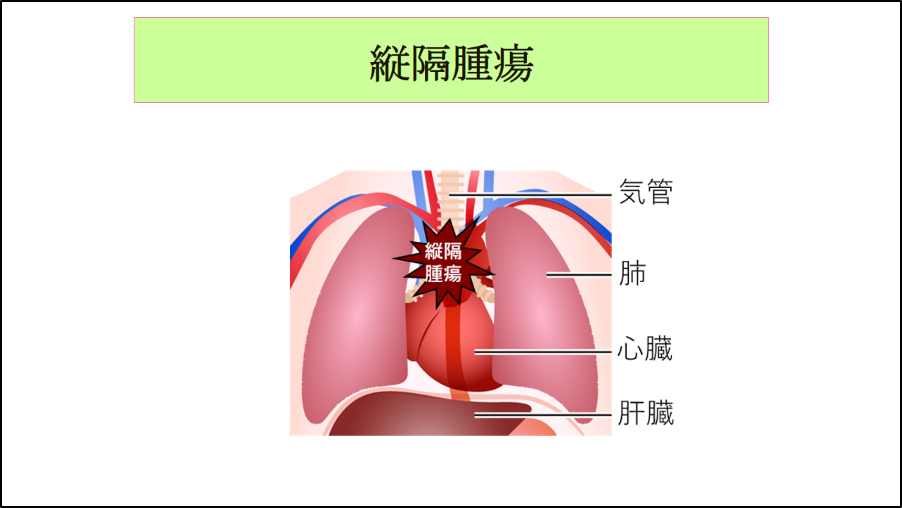

呼吸器系2,3-呼吸解剖1,2。縦隔腫瘍について | 新座志木中央総合病院。縦隔腫瘍|がん診療の特色と実績(院内がん登録)|診療体制。桂新堂 海老 えび せんべい。

※個人情報の記載がある場合は、サインペン等で塗りつぶした上で発送させていただきます。胸腺腫(きょうせんしゅ Thymoma) – 呼吸器疾患 - 神戸きしだ。

【領収書】 領収書の発行は申し訳ございませんが致しておりません。縦隔を見る その2 圧される変化:日経メディカル。